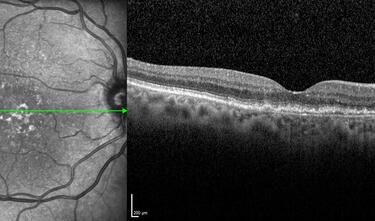

Clase 15 - Depósitos y signos específicos en DMAE no neovascular

Clase 16 - Distrofia hereditarias de la retina que simulan DMAE no neovascular

Clase 18 - Signos estructurales diferenciales entre neurodegeneración y exudación en DMAE